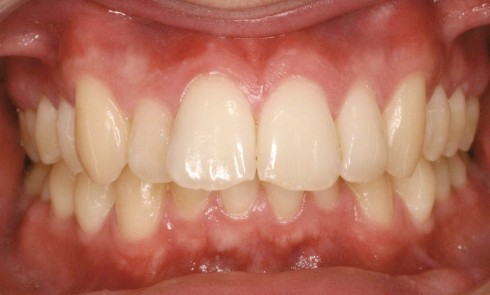

Article réservé à nos abonnés Facettes en céramique et gingivectomies : une approche a minima

Le sourire harmonieux est le fruit d’un équilibre complexe impliquant le positionnement des dents, leur couleur, leur forme et leur...